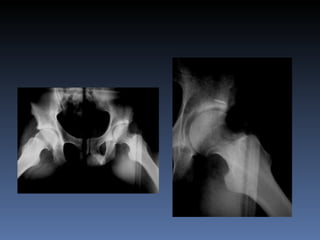

Un paciente de 25 años que trabaja como bodeguero ha experimentado dolor en su cadera derecha durante un año, empeorado por estar sentado o acostado. Su arco de movilidad articular está limitado, especialmente la rotación interna. Una artroresonancia y radiografías posteriores a la cirugía se realizaron para diagnosticar y tratar el problema.